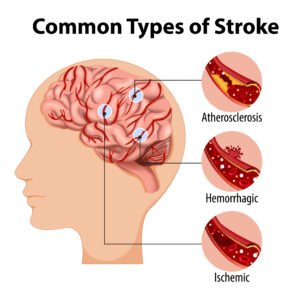

- Stroke